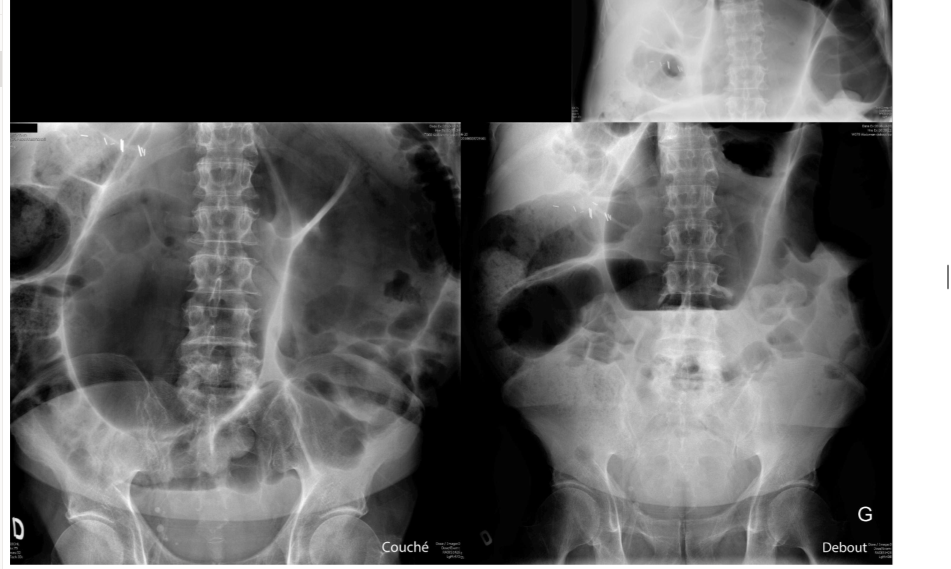

diagnostic?

A

volvulus pck immense